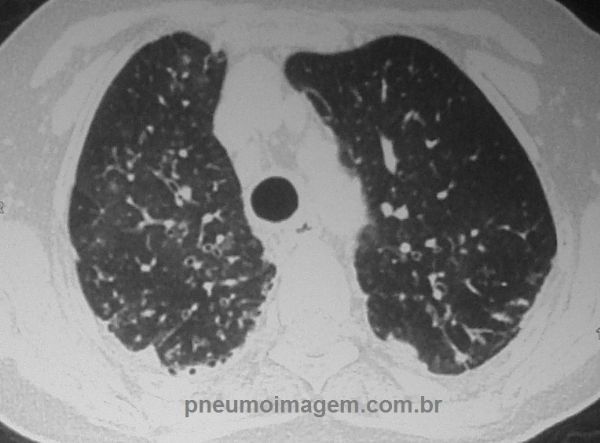

No corte na altura da carina observa-se a presença de bronquiectasias (sinal do trilho de trem) e nódulos centrolobulares difusos.